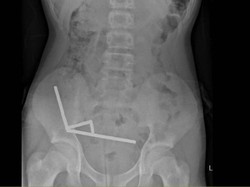

Seorang Remaja Telan Hampir 200 Magnet, Sebagian Usus Hilang

Remaja di Selandia Baru menelan hampir 200 magnet dan belum diketahui alasannya. Operasi dilakukan dan dia harus kehilangan sebagian usus.